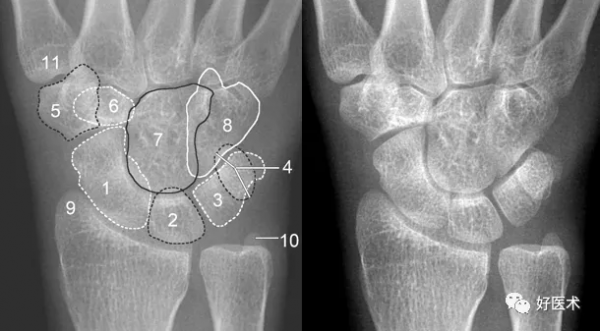

成人期腕關節正側位及舟骨蝶位片

1.舟骨 2.月骨 3.三角骨 4.豆狀骨 5.大多角骨 6.小多角骨 7.頭狀骨 8.鉤骨 9.橈骨莖突 10.尺骨莖突 11.第一掌骨基部

月骨形狀

不同體位月骨形狀

月骨呈梯形,近側邊緣平行於遠側邊緣。月骨若傾斜則呈三角形。僅透過此形狀的變化還不能判斷月骨是否脫位,因為位置改變,月骨形狀也會改變(圖)。可能是月骨脫位伴傾斜或僅僅是傾斜。